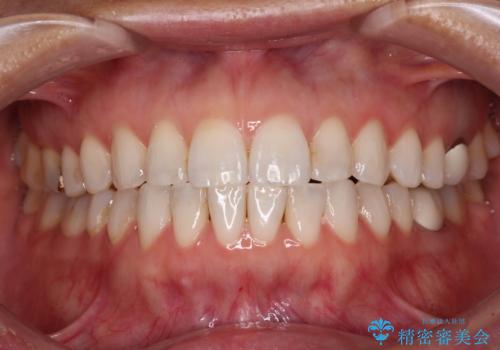

[ 前歯開咬 ] 前歯が噛んでいない マウスピース矯正治療

![[ 前歯開咬 ] 前歯が噛んでいない マウスピース矯正治療の症例 治療後](https://seimitsushinbi.jp/wp/wp-content/uploads/2022/11/IMG_2488-500x350.jpg?v=1668218373)